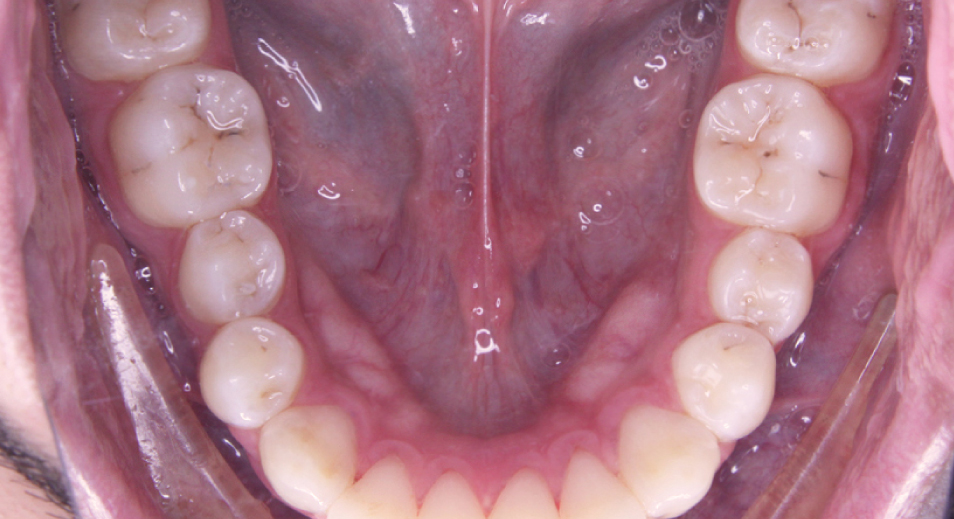

Fotografía Médica odontológica intra y extraoral

Registro fotográfico que se toma antes y después de los tratamientos odontológicos. sirve para evaluar y captar los rasgos intraorales y las características faciales.

Estas imágenes se emplean al iniciar el tratamiento mostrando el estado actual de la boca del paciente, se utilizan también para llevar un seguimiento y comparar luego del tratamiento para mostrar los resultados obtenidos.